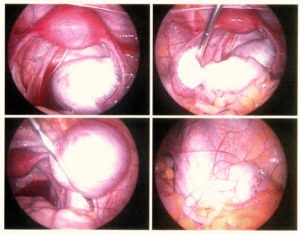

Tvrdošíjné buňky

Lauru dokonce její lékař nařkl z promiskuity, a než začal její příznaky brát vážně, poslal ji na kliniku pohlavních nemocí. Laparoskopie odhalila na jejích vaječnících, děloze, močovém měchýři, střevech a v Douglasově prostoru čtvrté stádium endometriózy. Zbloudilá endometriální tkáň byla chirurgicky odstraněna.